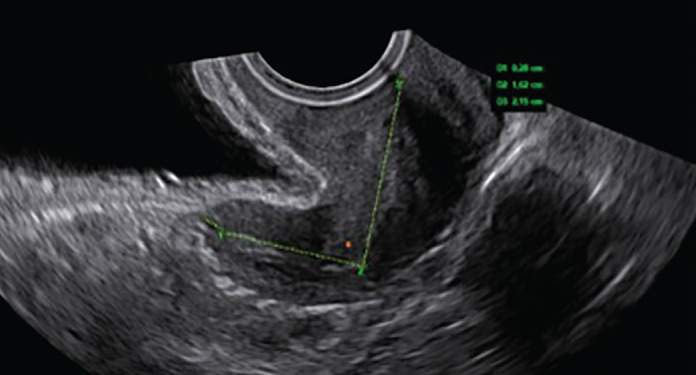

Results: The review revealed distinct characteristics of infantile uterus and uterine hypoplasia. The infantile uterus has a body/cervix ratio of 1:1 or 1:2, resembling that of a prepubescent girl, while uterine hypoplasia maintains a normal body/cervix ratio of 2:1 but is smaller in size. Diagnostic criteria include a total uterine length of less than 6 cm and specific ultrasound features such as reduced intercornual distance. Therapeutic options include hormonal therapy, particularly oestrogen administration, and surgical interventions aimed at expanding the uterine cavity. Hormonal treatments showed variable effectiveness, primarily beneficial in cases of oestrogen deficiency, while surgical approaches demonstrated some success in enhancing fertility outcomes in women with a hypoplastic uterus.